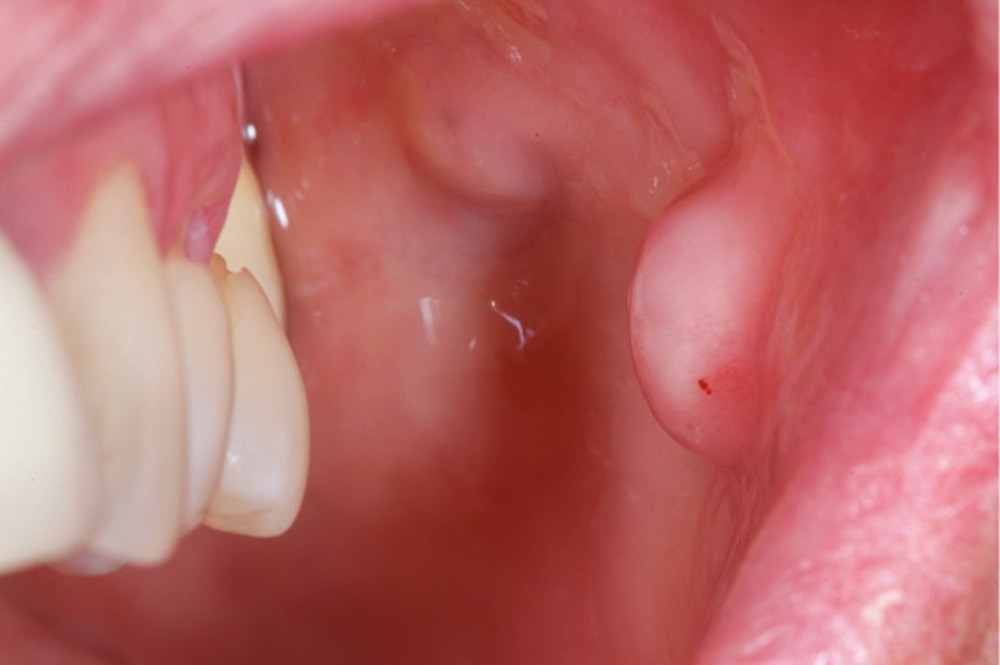

Conséquences muqueuses [11, 12]

Une extraction non compensée entraîne une vacuité de l’arcade par laquelle la muqueuse peut être « aspirée ». Il en résulte une excroissance de la joue ou de la lèvre par exemple, de forme sphérique le plus souvent. Il s’agit d’une tumeur bénigne correspondant à une hyperplasie fibro-épithéliale. Cette hyperplasie peut être retirée, mais il y aura récidive jusqu’au rétablissement de la continuité de l’arcade. Cela peut être gênant esthétiquement, mais peut aussi être à l’origine de morsures lors de la phonation ou de la mastication (fig. 20 et 21).